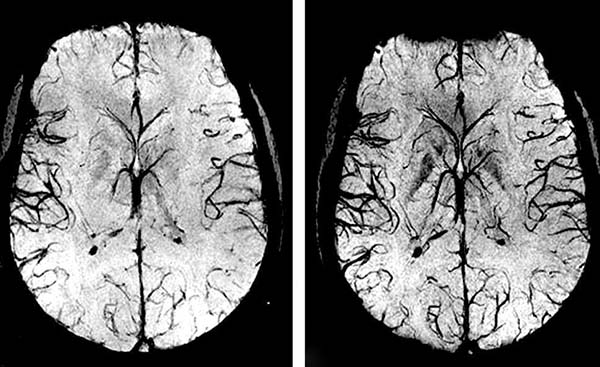

- Zerebrovaskuläre Erkrankungen. Es handelt sich um eine Unterbrechung der Blutgefäße im Gehirn, die zu einer mangelnden Versorgung der Gehirnzellen und damit zu einer Schädigung der Gehirnsubstanz führt. Dies führt häufig zu einem Schlaganfall, der zum Tod oder zu Behinderungen führt.

Und Blutgefäße, die an Kapazität verloren haben und das Gehirn nicht mehr richtig mit Blut

versorgen, sind ein sicherer Weg zum Schlaganfall.